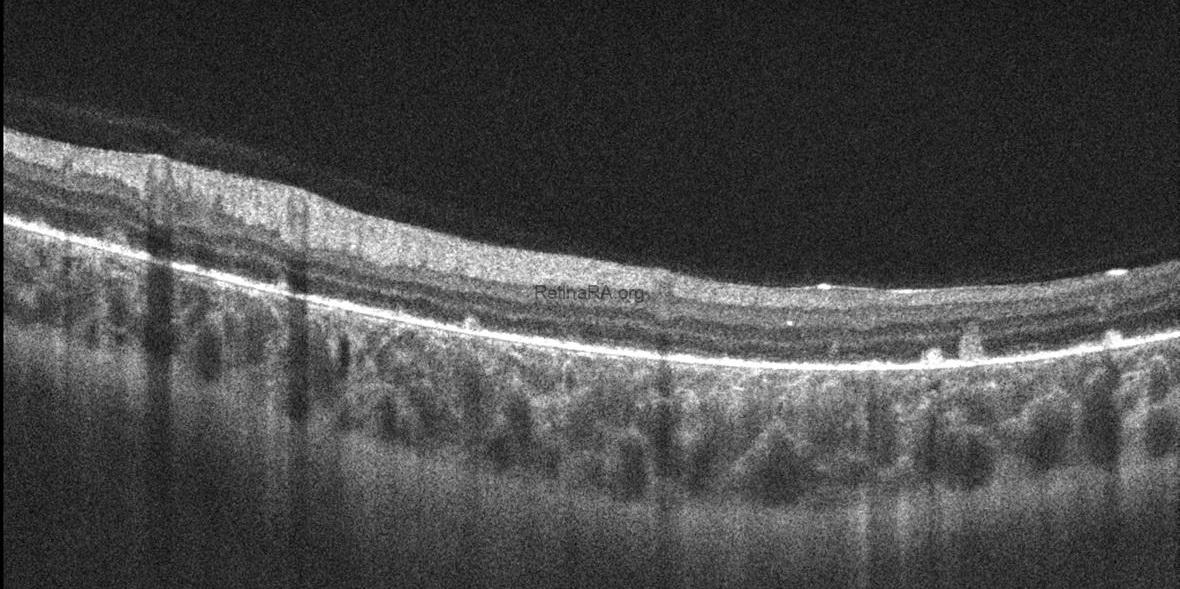

Optical coherence tomography (OCT) imaging showed bilateral hyperreflective dots in the inner retinal layers, bright reflective deposits in the RPE-Bruch membrane complex, and the absence of outer retinal tubulations. Among degenerative retinal diseases, the frequency of outer retinal tubulations is highest in Bietti crystalline dystrophy. However, retinal atrophy must be evident for outer retinal tubulations to appear. Therefore, this finding may not be seen in early-stage disease. The ellipsoid zone, interdigitation zone, and RPE disruption were more prominent on parafoveal OCT scans. The presence of prominent crystalline retinal deposits, together with the FAF and OCT findings, led to the diagnosis of early-stage Bietti crystalline dystrophy in this patient.

OCT of early-stage Bietti Crystalline Dystrophy